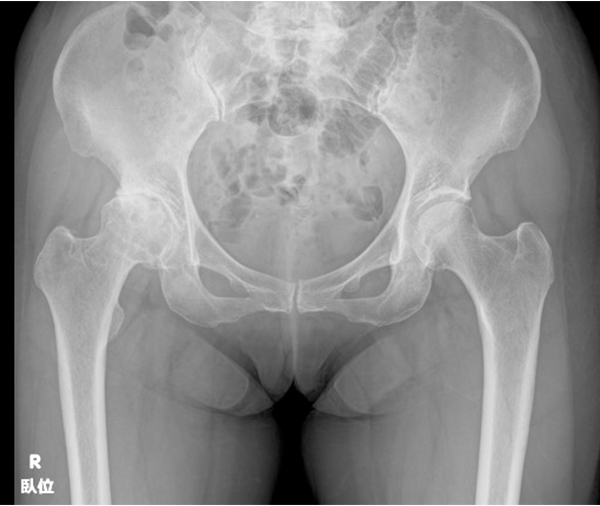

Q.「人工股関節置換術」について教えてください

人工股関節は金属製(コバルトやチタン合金)のステムとソケット、ポリエチレン製のライナー、セラミック製の骨頭で構成されています。 当院ではライナーに耐摩耗性に優れた超高分子ポリエチレンを使用しています。また、接着剤として骨セメントを使用するタイプと使用しないタイプがあり、当院では原則セメントを使用しないタイプを採用しています。